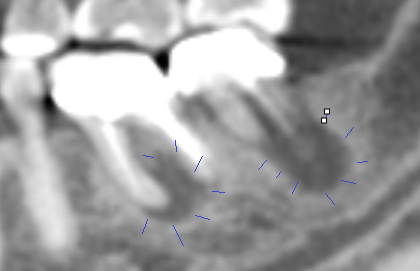

Case 8: CBCT is used weekly to evaluate root end abscess of dead, infected and broken teeth.